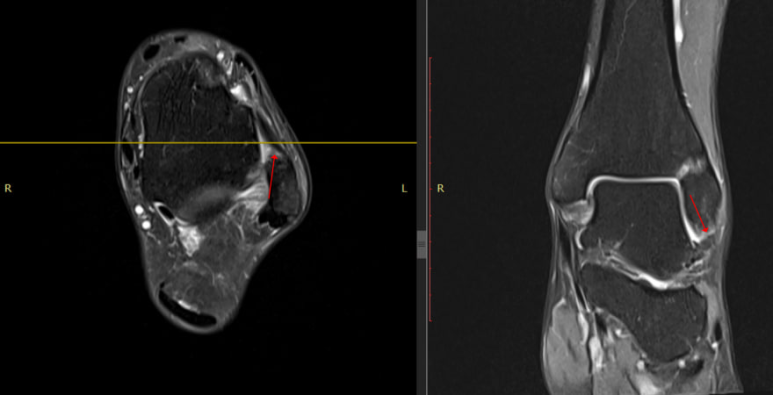

MRI 검사에서 인대파열로 진단

잘 낫지 않아

지역 2차병원에서

MRI 검사를 받으셨고

영상CD와 판독소견서를

가져오셨습니다.

영상의학과에서

발목 전거비인대 중에

비골에 붙는 곳이

부분 파열된 상태이며

주변 관절에도 염증이 있다는

소견을 받으셨습니다.

제가 MRI 영상을 참고해서

해당 혈자리를 꼼꼼하게 진찰해보니

한의학의 구허혈을 눌렀을 때

아주 심한 통증이 나타났습니다.